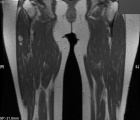

40 year old female presents with c/o burning/stabbing pain in her R anterolateral thigh. Pain has been present intermittently for >15 yrs, but has recently increased in intensity and frequency.

Zoom image: Radiological image Radiological image.